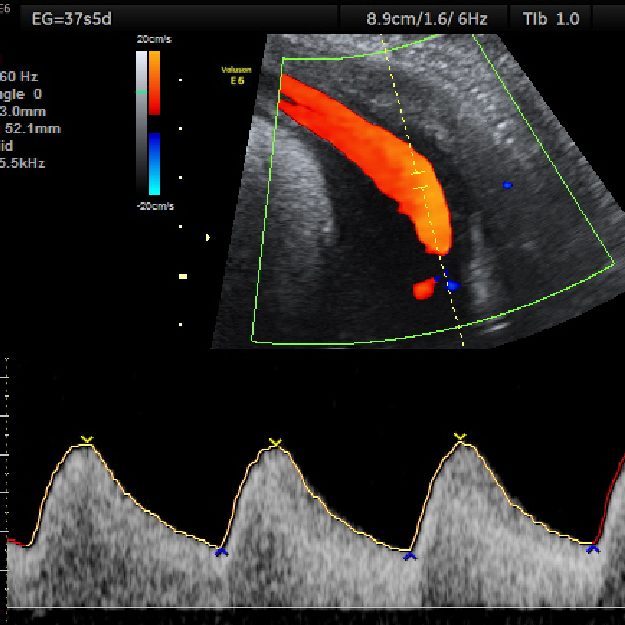

3. Confirmación de la vitalidad (latido cardíaco en el embrión/feto).

El ultrasonido es una técnica de diagnóstico por imagen; generada por de ondas de sonido que viajan a través de tu pancita, estas ondas de sonido son inofensivas para tu bebé, y nos permiten "fotografiar" y medir varias estructuras en formación.